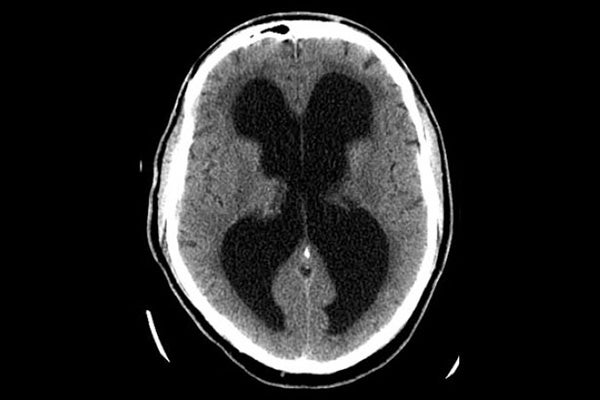

Erweiterte Hirnkammern mit zuviel Hirnwasser

Normale Hirnkammern

Es gibt im Wesentlichen zwei bildgebende Verfahren, deren Ergebnis den Verdacht NPH verstärken können:

• cMRT (kraniale Kernspintomographie)

• cCT (kraniale Computertomographie)